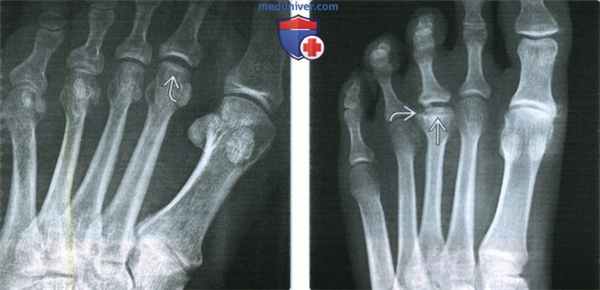

2. Рентгенография при болезни Фрейберга:

• Нарушение структуры головки плюсневой кости:

о Чередование очагов затемнения и просветления в головке плюсневой кости

о Извитая или чашеобразная линия затемнения под суставной поверхностью

• Патологический контур головки плюсневой кости:

о Уплощение головки плюсневой кости:

- Может быть вариантом нормы; у лиц без клинической симптоматики встречается в 10% случаев

о Вогнутость суставной поверхности головки плюсневой кости свидетельствует о поздней стадии болезни Фрейберга:

- Уплощение центральной части головки плюсневой кости может сочетаться с заострением медиального и латерального ее краев

• Нестабильный фрагмент (поздняя находка):

о Обычно располагается дорсально; лучше всего виден при рентгенографии в косой проекции

(Слева) При рентгенографии среднего отдела стопы в передне-задней проекции определяются слабо заметные уплощение и затемнение головки 2-й плюсневой кости, обусловленные болезнью Фрейберга. Поскольку контур головки плюсневой кости может быть несколько уплощен и в норме, для постановки рентгенографического диагноза необходимо наличие субхондрального склероза или вогнутости суставной поверхности.

(Справа) При рентгенографии переднего отдела стопы в передне-задней проекции визуализируются уплощение головки 3-й плюсневой кости и ее субхондральный склероз, характерные для поздней стадии болезни Фрейберга. Чашеобразная линия затемнения является границей патологически измененной зоны.